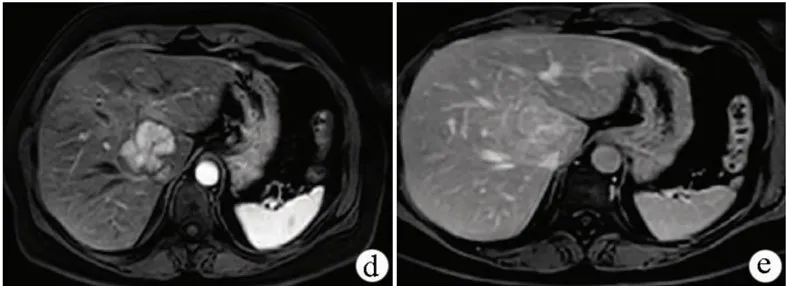

诊断 :FNH的诊断主要依靠影像学和分子病理学检查。常用的检查方法有超声、CT、MRI和血管造影等。联合应用可提高其确诊率。

图5 MRI图像

图6 造影剂增强图像